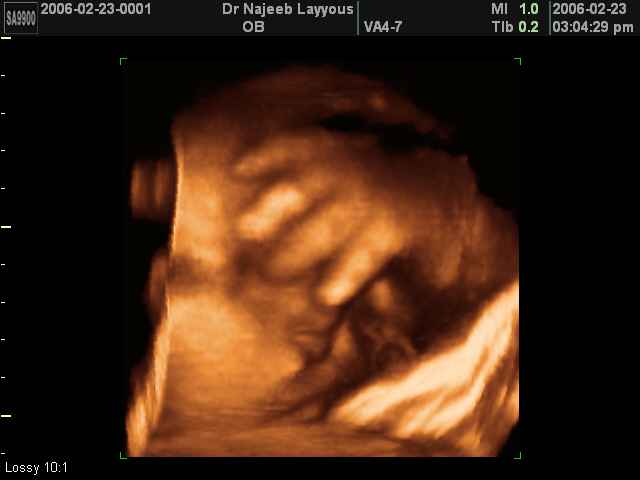

- تصرفات الجنين داخل الرحم

- إبدأي ألبوم صور طفلك معنا

- أهمية التصوير بالموجات فوق الصوتية رباعي الابعاد في الحمل 4D ultrasound

- لقطات فيديو للجنين بجهاز الموجات فوق صوتية رباعي الأبعاد

- صور لوجه الجنين في داخل الرحم

- صور لتصرفات الجنين داخل الرحم

صور لأطراف الجنين بجهاز الالتراساوند ثلاثي الأبعاد | الدكتور نجيب ليوس